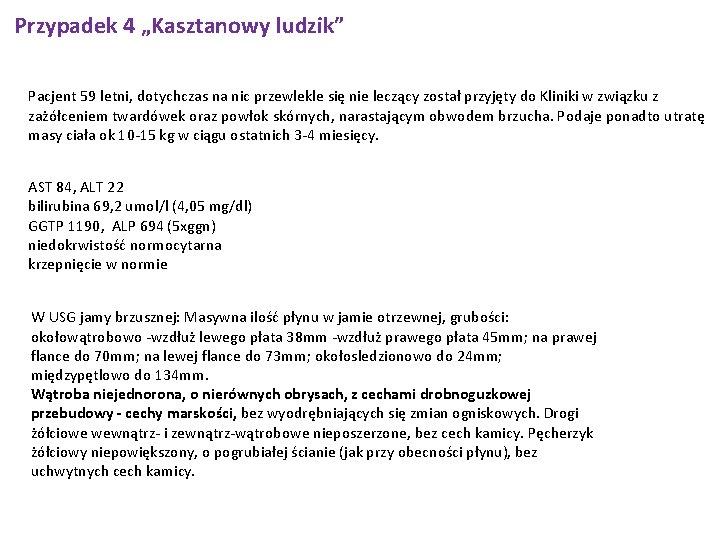

Przypadek 4 „Kasztanowy ludzik” Pacjent 59 letni, dotychczas na nic przewlekle się nie leczący został przyjęty do Kliniki w związku z zażółceniem twardówek oraz powłok skórnych, narastającym obwodem brzucha. Podaje ponadto utratę masy ciała ok 10 -15 kg w ciągu ostatnich 3 -4 miesięcy. AST 84, ALT 22 bilirubina 69, 2 umol/l (4, 05 mg/dl) GGTP 1190, ALP 694 (5 xggn) niedokrwistość normocytarna krzepnięcie w normie W USG jamy brzusznej: Masywna ilość płynu w jamie otrzewnej, grubości: okołowątrobowo -wzdłuż lewego płata 38 mm -wzdłuż prawego płata 45 mm; na prawej flance do 70 mm; na lewej flance do 73 mm; okołosledzionowo do 24 mm; międzypętlowo do 134 mm. Wątroba niejednorona, o nierównych obrysach, z cechami drobnoguzkowej przebudowy - cechy marskości, bez wyodrębniających się zmian ogniskowych. Drogi żółciowe wewnątrz- i zewnątrz-wątrobowe nieposzerzone, bez cech kamicy. Pęcherzyk żółciowy niepowiększony, o pogrubiałej ścianie (jak przy obecności płynu), bez uchwytnych cech kamicy.

Przypadek 4 30. 11. 2017 Wynik RTG klatki piersiowej PA i bok - płuca krótkie - zdjęcie na niepełnym wdechu. Płyn w lewej jamie opłucnej spłycający kat p-ż i zachyłek p-ż tylny. Nad jego poziomem zmiany niedodmowo-zapalne. Po stronie prawej kąt p-ż i przepona wolne. W prawym dolnym polu płucnym, obowodowo, zrosty. Poza tym pola płucne bez zmian ogniskowych, bez zastoju. W dolnym biegunie prawej wnęki wzmożony rysunek okołooskrzelowy, lewa wnęka nieposzerzona. Sylwetka serca nie do oceny. Aorta piersiowa w normie.

Przypadek 4 Epikryza Pacjent l. 59 bez chorób przewlekłych w wywiadzie został przyjęty z powodu zażółcenia powłok skórnych i twardówek, powiększenia obwodu brzucha oraz utraty masy ciała ok. 10 kg w ciągu 3 miesięcy. Pacjent podaje nadużywanie alkoholu. Przyjęty w stanie ogólnym średnim, przytomny, w pełnym kontakcie słowno-logicznym, skóra i twardówki nieznacznie zażółcone, wydolny krążeniowo i oddechowo, brzuch wysklepiony powyżej poziomu klatki piersiowej, bez objawów otrzewnowych, bez obrzęków obwodowych. W badaniach laboratoryjnych cechy toksycznego uszkodzenia wątroby, podwyższone parametry zapalne, wykluczono zakażenie wirusami HBV, HCV. W USG jamy brzusznej wątroba niejednorododna, o nierównych zarysach, z cechami przebudowy drobnoguzkowej. Włączono leczenie moczopędne, empiryczną antybiotykoterapię, dwukrotnie wykonano paracentezę (płyn puchlinowy bez cech zapalenia, posiew płynu ujemny, komórek atypowych nie stwierdzono). Po uzyskaniu poprawy stanu ogólnego pacjenta wypisano do domu w stanie ogólnym dobrym.